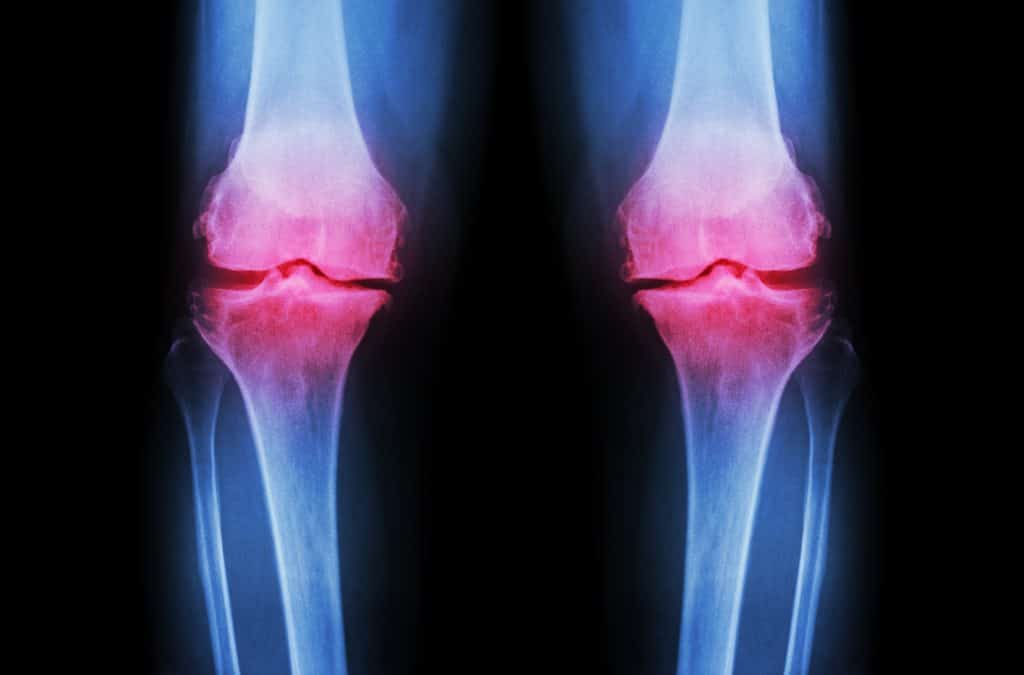

Degenerativne bolesti zglobova su kronične i degenerativne bolesti koje uzrokuju propadanje zglobne hrskavice. Osteoartritis poznat i pod imenom osteoartroza ili artroza najpoznatiji je oblik degenerativne bolesti zglobova. Ta je bolest nakon niza kardiovaskularnim problema i bolesti najčešći uzrok onesposobljenosti kod ljudi jer zahvaća zglobove kukova i koljena koji su izrazito važni za pokretanje. Uzročnici degenerativnih bolesti zglobova mogu biti mnogobrojni. Glavni uzroci su kombinacija više faktora koji uključuju životne navike i aktivnosti, genetsko naslijeđe, hormoni, mehanička oštećenja i traume te djelovanje nekih enzima i kemijskih spojeva koji se nalaze u tijelu. S obzirom na to, takve degenerativne bolesti koje zahvaćaju zglobove mogu biti podijeljene na primarni i sekundarni oblik koji se odnose na to kako je do tih oštećenja došlo. Primarni oblik ne povezuje se s vanjskim čimbenicima, dok se sekundarni oblik veže uz uzroke kao što su pretjerana tjelesna težina, traume zglobova, artritis ili neke infekcije te još niz raznih bolesti.

Degenerativne bolesti zglobova kreću na zglobnoj hrskavici. Te promjene najčešće su uzrokovane starenjem organizma ili određenim bolestima kada se na površini hrskavice trgaju kolagena i građevna vlakna zbog čega ona gube glatkoću. U zglobovima se nalazi takozvana zglobna tekućina čiji je zadatak poravnati neravnine na hrskavici, no prilikom prevelikih oštećenja hrskavice nema dovoljno te tekućine kako bi se ona zagladila zbog čega dolazi do dodatnog opterećenja pri pokretu. Ukoliko se hrskavica u potpunosti istroši, kosti dođu u dodir i takvi procesi uzrokuju upale koje uzrokuju daljnje promjene zbog čega se javljaju degenerativne bolesti zglobova. Osim što te promjene zahvaćaju same kosti, one se s vremenom prošire i na okolna tkiva kao što su ligamenti, okolna mišićna tkiva i slično. Navedeni degenerativni poremećaji javljaju se postupno i ne nastaju odjednom već je potreban duži niz godina da bi došlo do tog stanja. Stoga je važno pratiti simptome i raditi prevenciju ukoliko je to moguće.